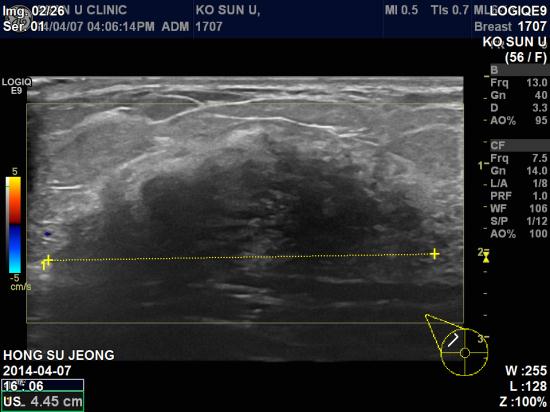

본원 초음파 상 우측유방 11시방향에 4.45 cm 의 종괴 및

우측겨드랑이의 림프절 비대소견.